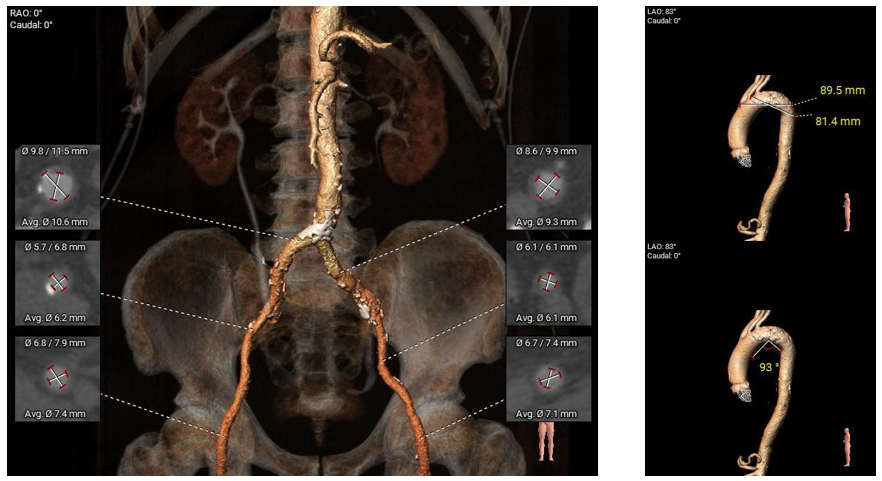

外周分析

外周概览(钙化)

外周概览

入路血管走形良好,无明显附壁钙化,弓部条件良好,预估过弓、跨瓣顺利。